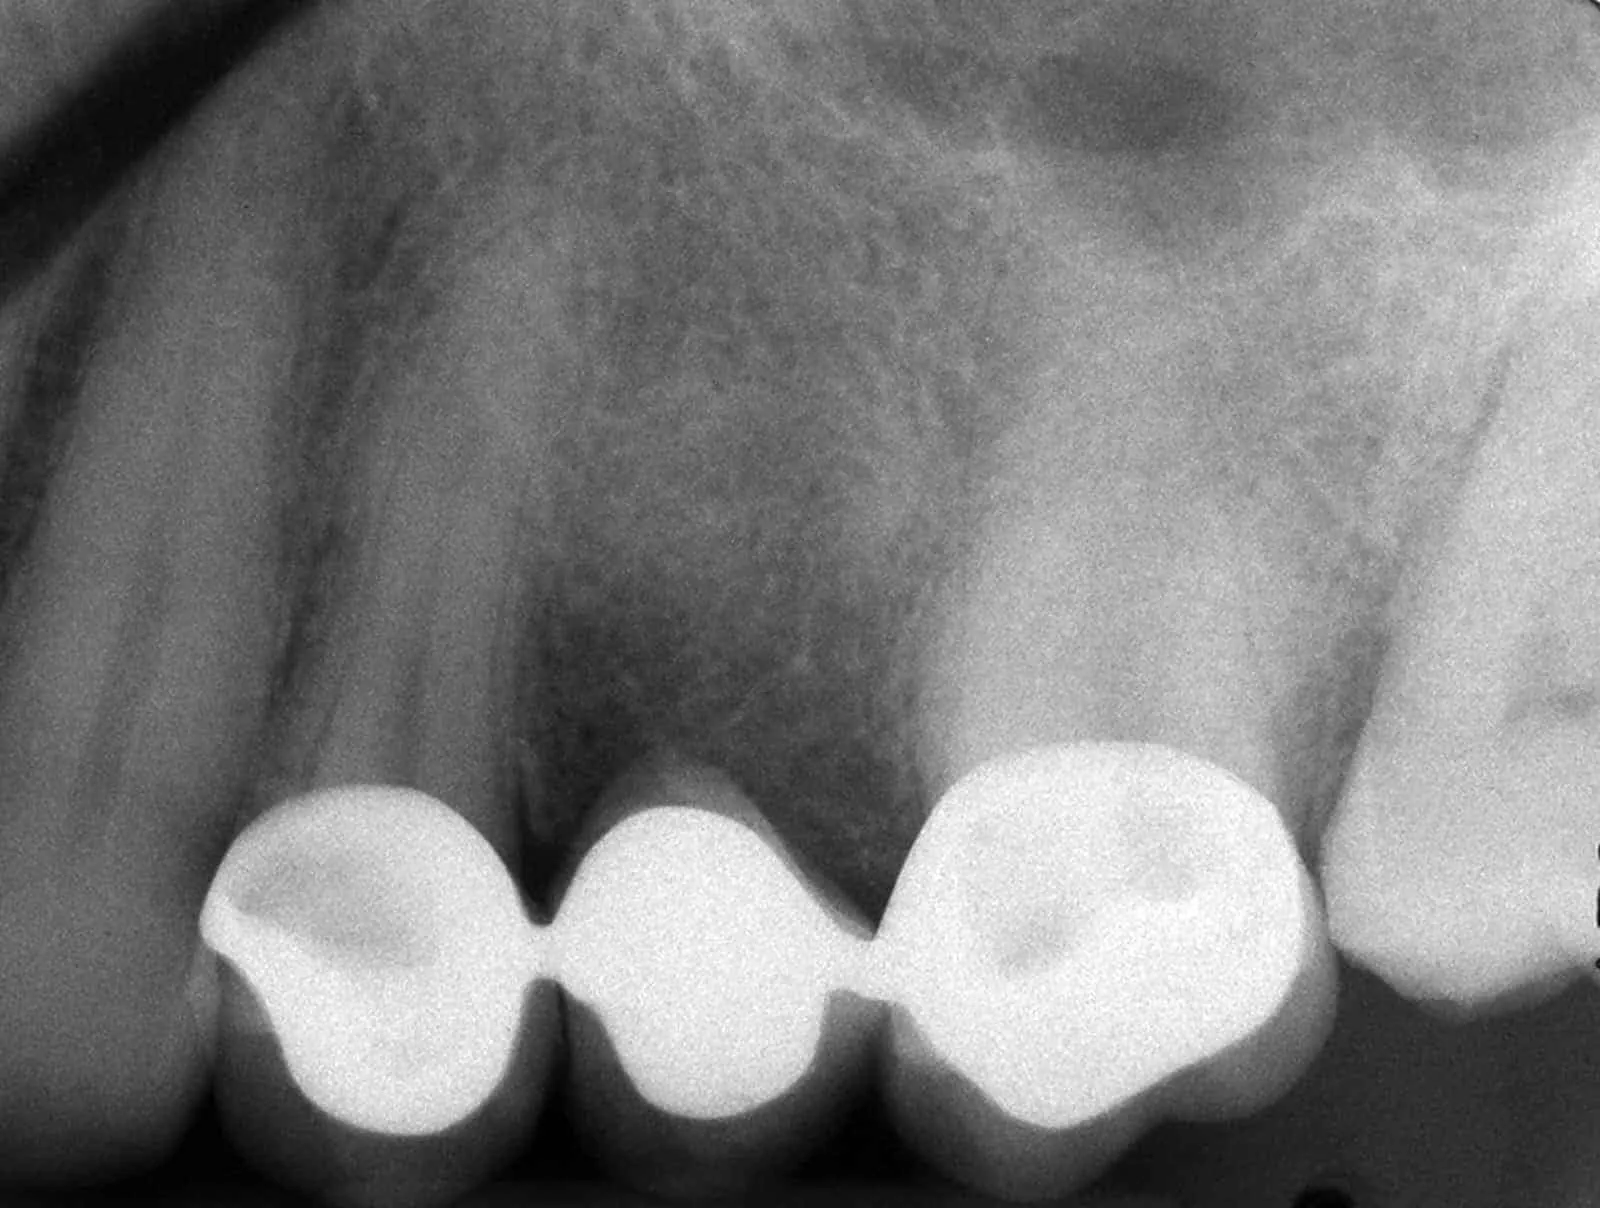

Before:Â Failed upper posterior three-unit bridge. Tooth #14 (upper left first molar) requires root canal therapy. Ideal candidate for a single dental implant to replace missing tooth #13 (upper left second premolar) and two single crowns on abutment/support teeth 12 (upper left first premolar) and 14. However, the patient is not interested in implant therapy and would like revision crown and bridge (fixed partial denture) therapy.

After:Â Revision crown and bridge therapy. Tooth #14 was carious and required root canal therapy and a build-up (foundation restoration) prior to definitive bridge therapy. Three-unit fixed partial denture (bridge), porcelain fused to gold, abutment teeth 12 and 14.